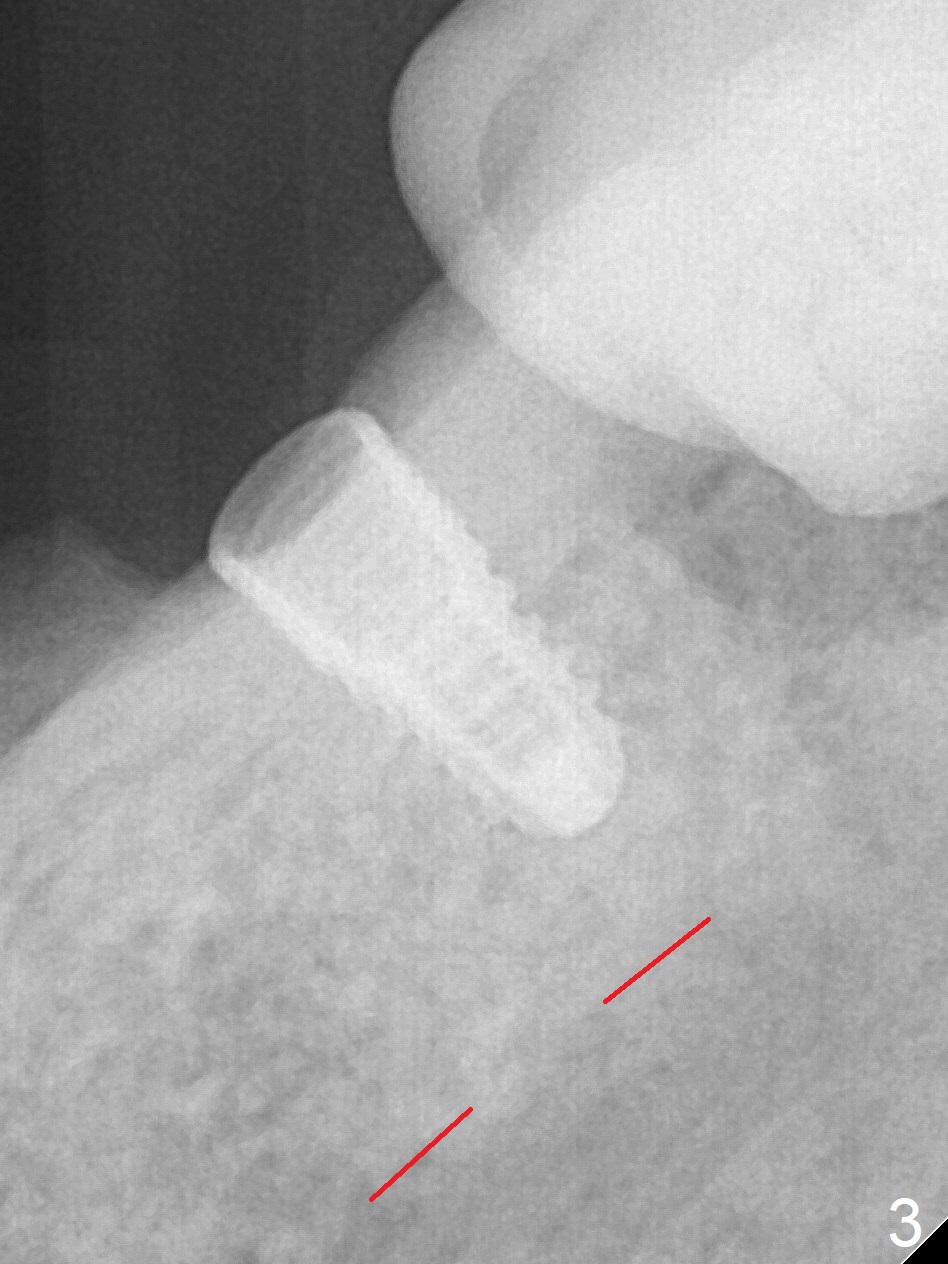

Preop photo confirms the lower left posterior pointed ridge (Fig.1). After ridge reduction and 2 mm drill for 8 mm, a parallel pin is inserted (Fig.2). A 3.8x8 mm SM implant is placed with >50 Ncm (Fig.3). The coronal threads (buccodistal) is covered with VeraGraft after placement of 4.1x5(3) mm healing abutment. The tooth #17 is not planned for extraction while the implant is osteointegrated. The tooth appears to be too loose and is extracted ~ 1.5 months postop. The implant seems to be osteointegrated 3 months postop (Fig.4). The healing abutment is changed to ball abutments with 4 mm (Fig.5) and 2 mm (Fig.6) cuffs. In fact the latter stays. What is the special device at the site of #18 (ring, Fig.7 <)?